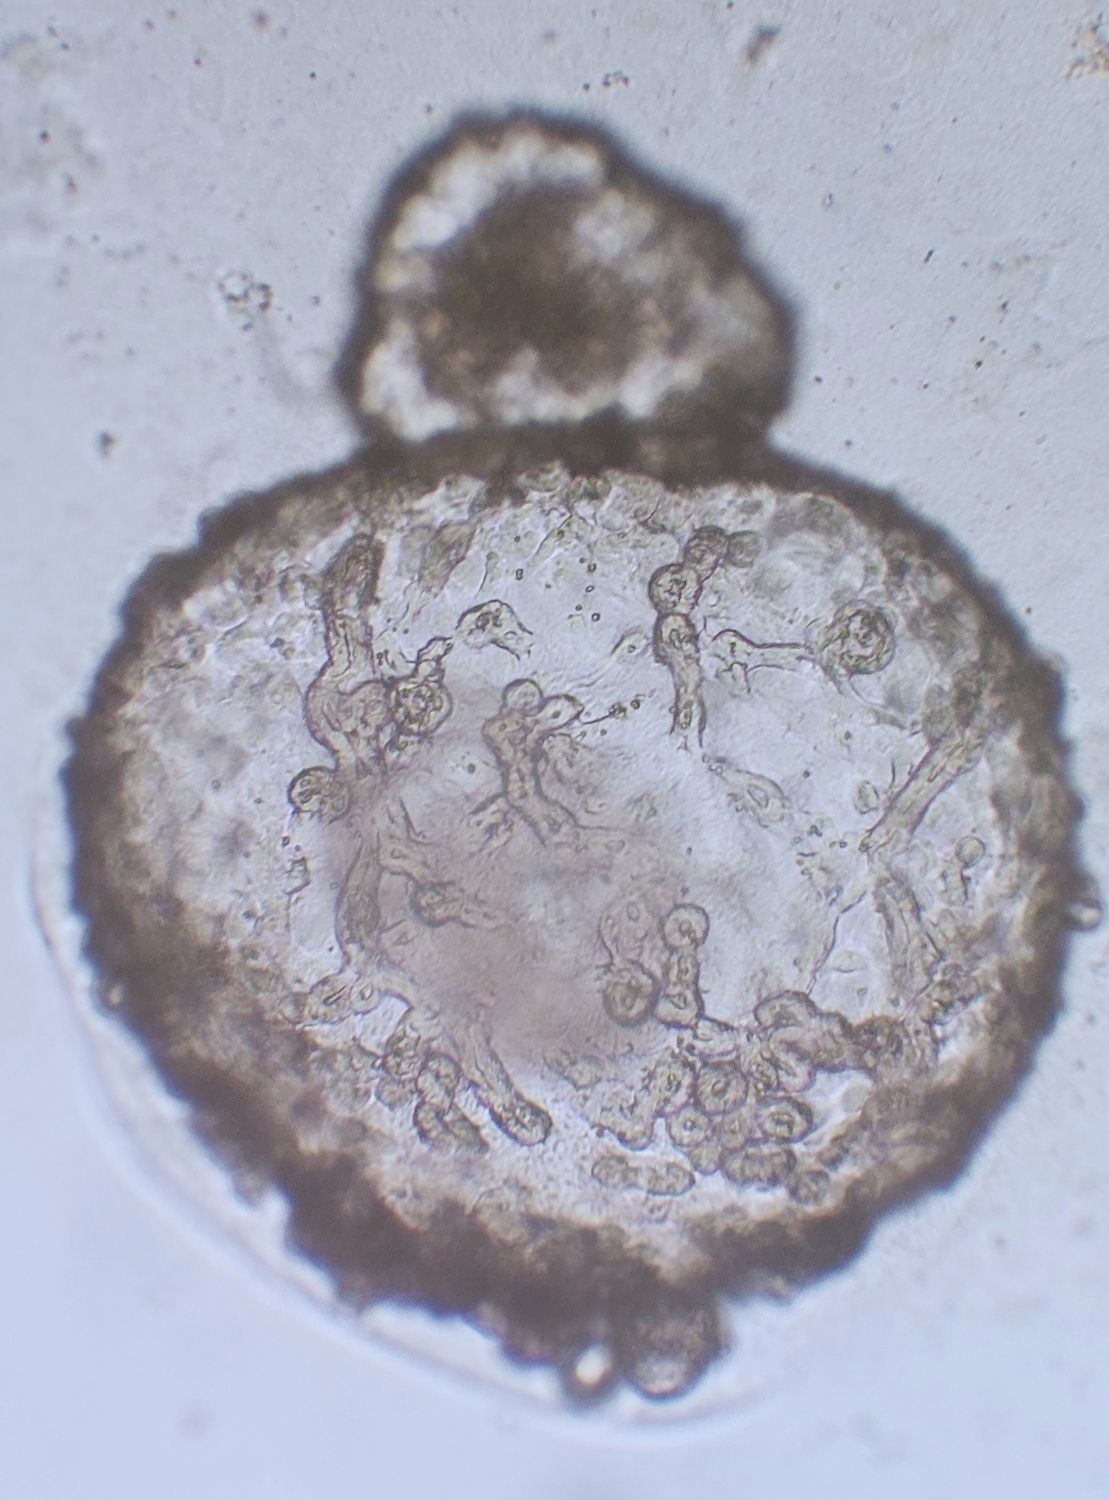

El cultivo de organoides es una tecnología emergente de cultivo 3D, procedente de diversos órganos y tejidos, como el cerebro, el intestino, el pulmón, el corazón, el hígado y el riñón. En comparación con el cultivo bidimensional (2D) tradicional, los sistemas de cultivo de organoides tienen la ventaja única de conservar la expresión génica parental, así como el mantenimiento a largo plazo de la función y las características biológicas de las células parentales in vitro.

El principal objetivo del curso es incentivar el uso de métodos alternativos en experimentación animal, a través de cultivos 3D en Biomedicina, una técnica innovadora que simula de manera más efectiva el entorno celular in vivo. Los participantes aprenderán a preparar cultivos primarios de organoides de intestino de ratón y cultivos de esferoides de líneas celulares humanas, desarrollando habilidades prácticas fundamentales en el campo biomédico.

Además, el curso abordará el uso de organoides intestinales de ratón para determinar la toxicidad de compuestos químicos, ofreciendo una aplicación práctica y relevante de las técnicas aprendidas. Los participantes también explorarán otros usos potenciales de los esferoides y organoides en investigación biomédica.